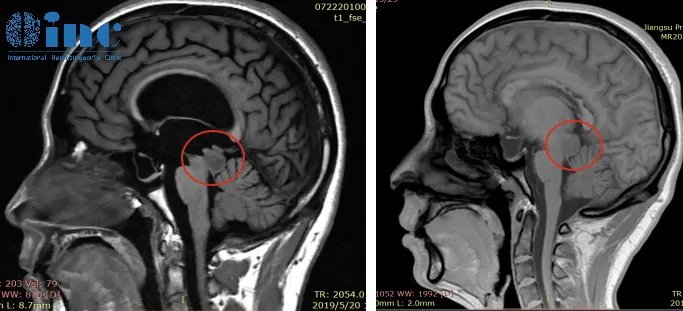

“我研究了这名年轻患者2019年5月20日的医疗报告和磁共振图像。它们显示了中脑顶盖内的病变,有可能是低级别的胶质瘤。我已经成功地对许多相似的肿瘤病人进行了手术,并发表了我的研究结果和临床技术。如果患者希望阅读这本描述成人患者脑干胶质瘤的治疗出版物,我可以发送我的书章节的PDF文件。”

2019年6月,巴教授在苏州为峥峥手术,肿瘤全切,无任何神经功能损伤,病理结果显示:(四叠体区)星形胶质细胞瘤(WHOⅡ级)。

术后MRI影像